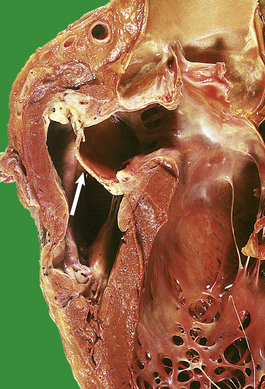

Aortic dissection (dissecting aneurysms)

In aortic dissection, blood is forced through a tear in the aortic intima to create a blood-filled space in the aortic media (Fig. 13.9). This can track back into the pericardial cavity, causing a fatal haemopericardium, or can rupture through the aortic adventitia. In occasional cases the track re-enters the main lumen to create a ‘double-barrelled’ aorta. The intimal tear and the anatomical features of the aorta can be demonstrated in life by CT or MRI scanning. The underlying pathology is poorly understood. In some, but by no means all, cases there is pronounced degeneration of the aortic media. This is the so-called cystic medial necrosis and is characterised by mucoid degeneration and elastic fibre fragmentation. An exaggerated form of this change is seen in Marfan’s syndrome, a congenital disorder of the expression of a glycoprotein, fibrillin, closely associated with elastin fibres. The strongest risk factor for dissecting aneurysm is systemic hypertension. In some cases the intimal ‘entry’ tears are around atheromatous plaques, but in most cases they involve disease-free parts of the aorta. Without treatment, the mortality from dissecting aneurysm is at least 50% at 48 hours, and 90% within 1 week. The immediate aim of treatment is to contain the propagating haematoma by reducing arterial pressure. Surgical repair is feasible in some patients, especially if the process affects the proximal aorta.

image

Fig. 13.9 Aortic dissection. image A CT scan of a patient with an acute dissection of the ascending aorta. There are two patterns of contrast enhancement in the aorta. The whiter is the main lumen and the greyer the false lumen. image The innermost portion of the aortic wall has been peeled away to reveal the underlying haemorrhagic tract.